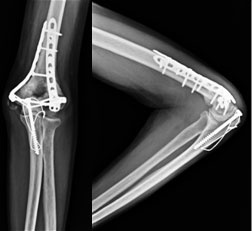

1 ½ year post surgery

The fracture healed well as seen in the xrays. The implants are still holding well. We do not recommend implant removal routinely unless the implant is causing any trouble. |